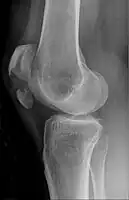

Osteochondral fracture of patella